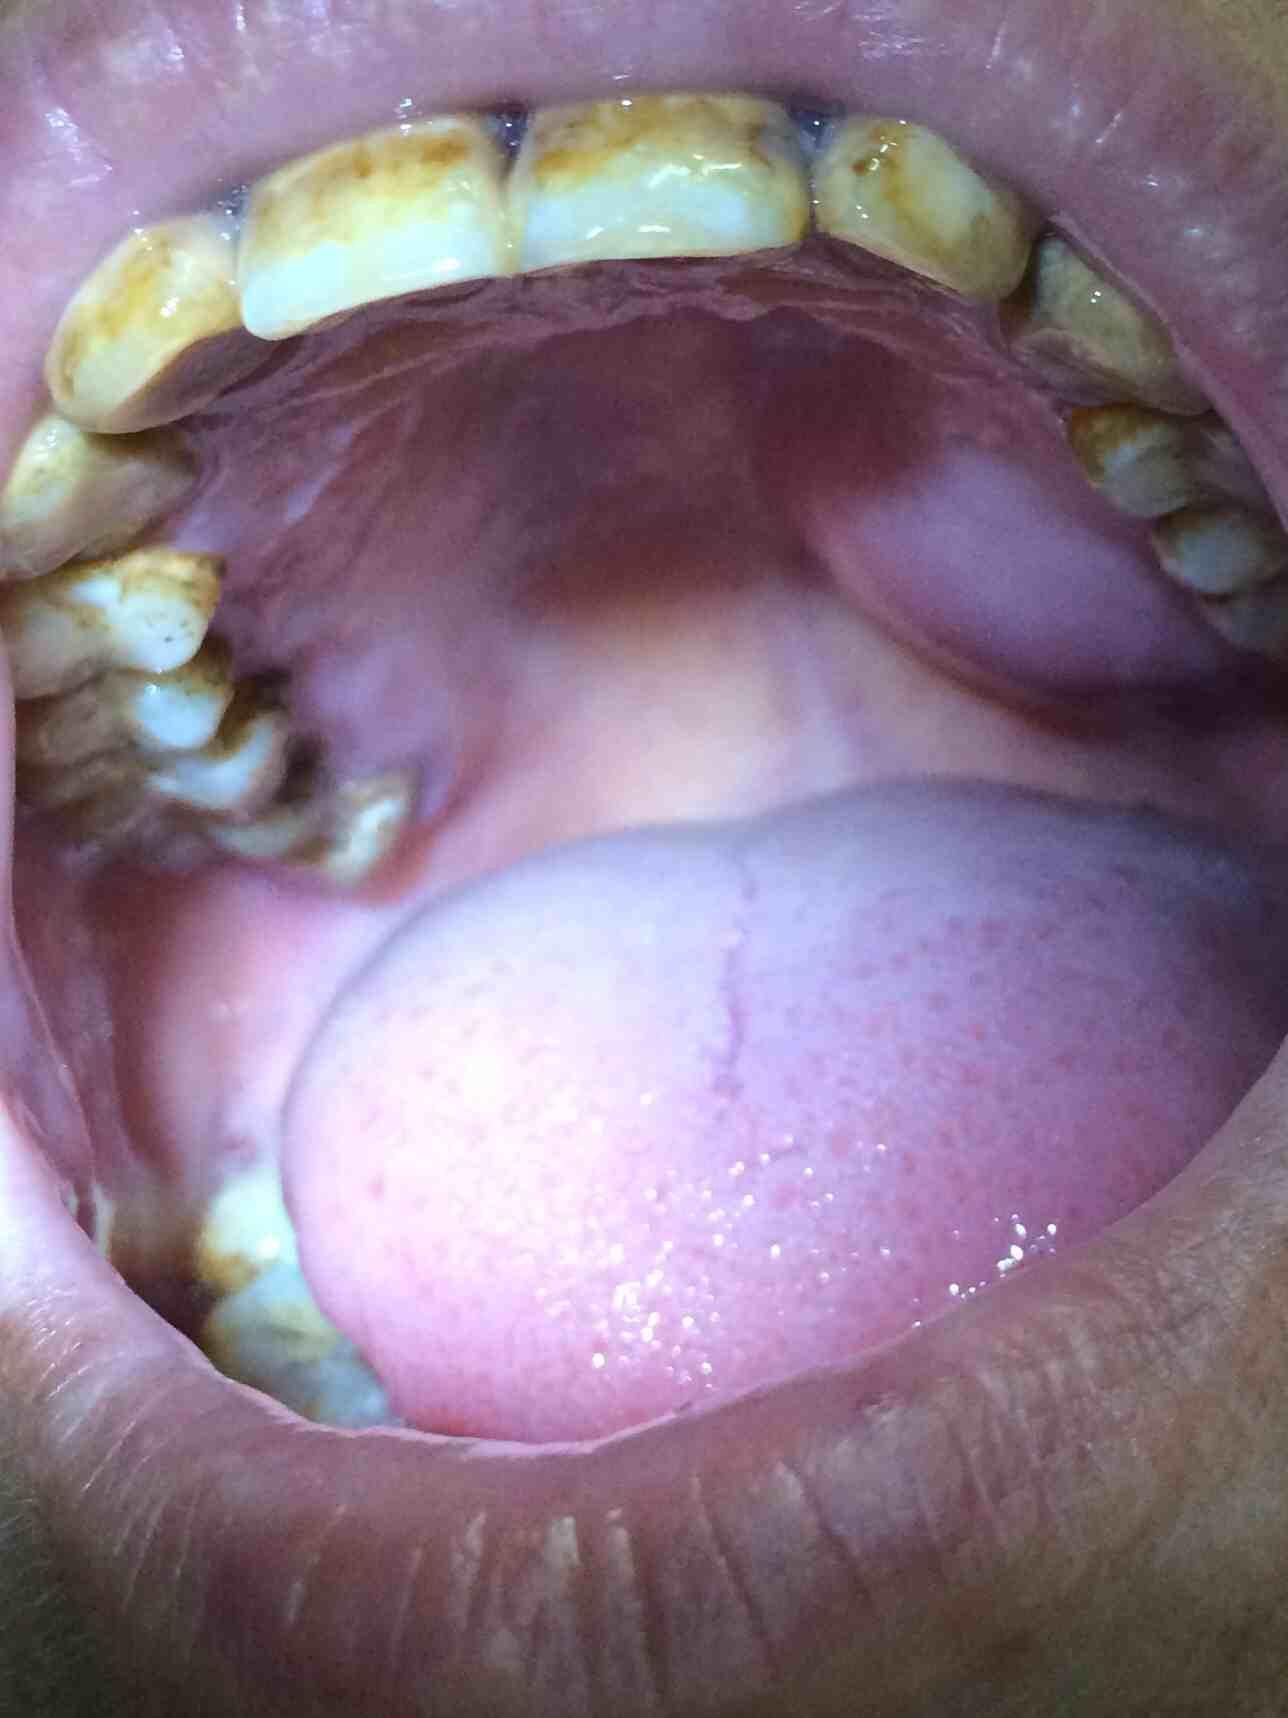

患者7,8年前口腔左上腭开始长肿块,进展缓慢,不痛,无其他不适,饮食正常,无消瘦。请大家帮忙诊断一下。

同意混合瘤

肿块取样病检,鉴别良/恶性